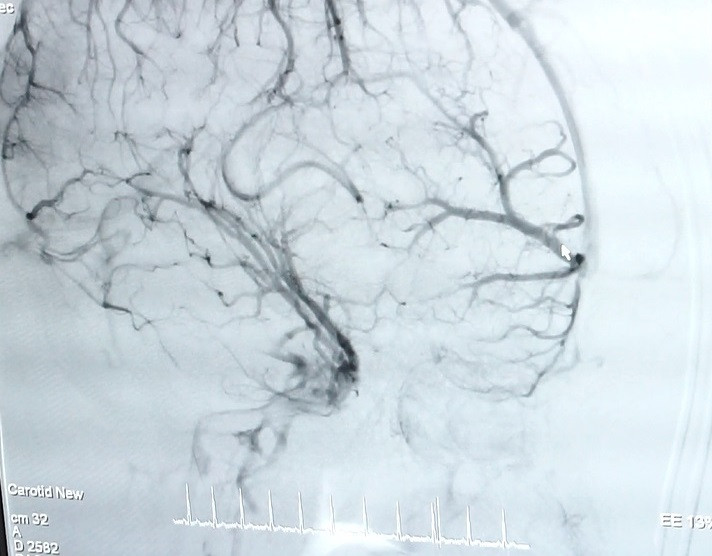

Kết quả chụp CT não tại Bệnh viện Quốc tế City cho thấy,bệnh nhân bị xuất huyết não thái dương trái – não thất nghi ngờ do vỡ dị dạng mạch máu não. bệnh nhân được TS.BS Trần Chí Cường, cố vấn chuyên môn tại Trung tâm đột quỵ CIH- SIS chụp mạch máu não bằng ứng dụng công nghệ cao – DSA nhằm phát hiện những bất thường của mạch máu.

Theo TS.BS Trần Chí Cường, dị dạng mạch máu (AVM) vô cùng nguy hiểm bởi có thể gây ảnh hưởng đến chi phối của não bộ lên hoạt động cơ thể, nếu phát hiện và điều trị muộn có thể dẫn đến tử vong. Bệnh nguy hiểm nhưng nếu được chẩn đoán sớm có thể điều trị khỏi hoàn toàn. Hiện nay, phương pháp chụp mạch máu não bằng ứng dụng DSA giúp bác sĩ có cái nhìn chính xác về vị trí, kích thước, hình dạng của đoạn mạch dị dạng đồng thời vẽ được biểu đồ huyết mạch nơi mạch máu dị dạng phát sinh.

Nôn ói cứ ngỡ trúng thực, bệnh nhân suýt chết vì xuất huyết não ảnh 2Hình ảnh mạch máu não của bệnh nhân N.